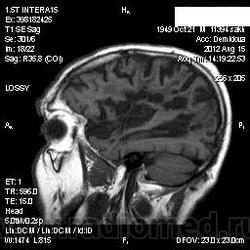

1 случай -локальная гемиатрофия.2 случай-диффузная.

Молодой человек после автомобильной аварии.3 года лежит.Двигаются только глаза.Зрелище душещипательное.

Евгений, конечно же, мои случаи не являются "чистой" атрофией-согласна.Мне пока не встречались случаи болезни Пика, Альцгеймера и другие "чистой воды" атрофии.Второй случай- состояние после длительной комы вследствие автодорожной травмы 3 года назад.Пациент проходил исследование в прошлом году , в этом родители привезли на динамику.